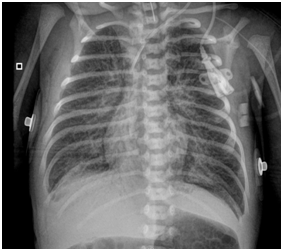

However, on day … episodes of desaturation appeared with an increase in FiO2 and ON up to 40ppm, and the patient remained under sedation. On the sixth day, milrinone was added to improve perfusion at the pulmonary level and norepinephrine was reinitiated to increase systemic blood pressure. In addition, a dose of surfactant was administered, chest radiography showed bilateral parahiliar interstitial infiltrate, peripheral pulmonary vasculature increased, and decrease in left cavities (Figure 3). Nevertheless, within a few hours she had bradycardia and hypotension, and a new echocardiogram was performed, evidencing right chambers failure and an advanced resuscitation was initiated with drug administration and cardiac massage without obtaining a response, causing patient´s death. The transfontanelar scan was normal. A karyotype was done with a normal report (46,XX).

Figure 3 Chest x-ray with pulmonary changes by HTPP.